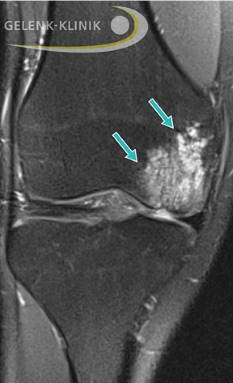

MRT-Darstellung Knie: Die Osteochondrosis dissecans wird von einem ausgeprägten Knochenmarködem begleitet. © Gelenk-Klinik

Für die exakte Diagnose einer Osteochondrosis dissecans ist die Magnetresonanztomographie (MRT) am besten geeignet. Durch diese Untersuchung bestimmt der Arzt die Größe des erkrankten Knorpel-Knochen-Fragments.

Die MRT erfasst präzise den Status des Gelenkknorpels. Ein Ödem des subchondralen Knochens, freie Gelenkkörper oder ein Gelenkerguss werden gut dargestellt. Durch die MRT-Aufnahmen kann der Facharzt die Stabilität oder Instabilität der Osteochondrosis dissecans beurteilen.

Die MRT bietet eine exakte Einschätzung des OD-Stadiums vergleichbar mit den Ergebnissen einer Kniespiegelung (Arthroskopie). Die Untersuchungsergebnisse geben dem Facharzt wichtige Hinweise für die Prognose der vorliegenden OD. Die MRT-Befunde sind entscheidend für die Wahl der Therapie. Außerdem ermöglicht die MRT dem behandelnden Arzt, den Heilungsprozess der OD zu überwachen.